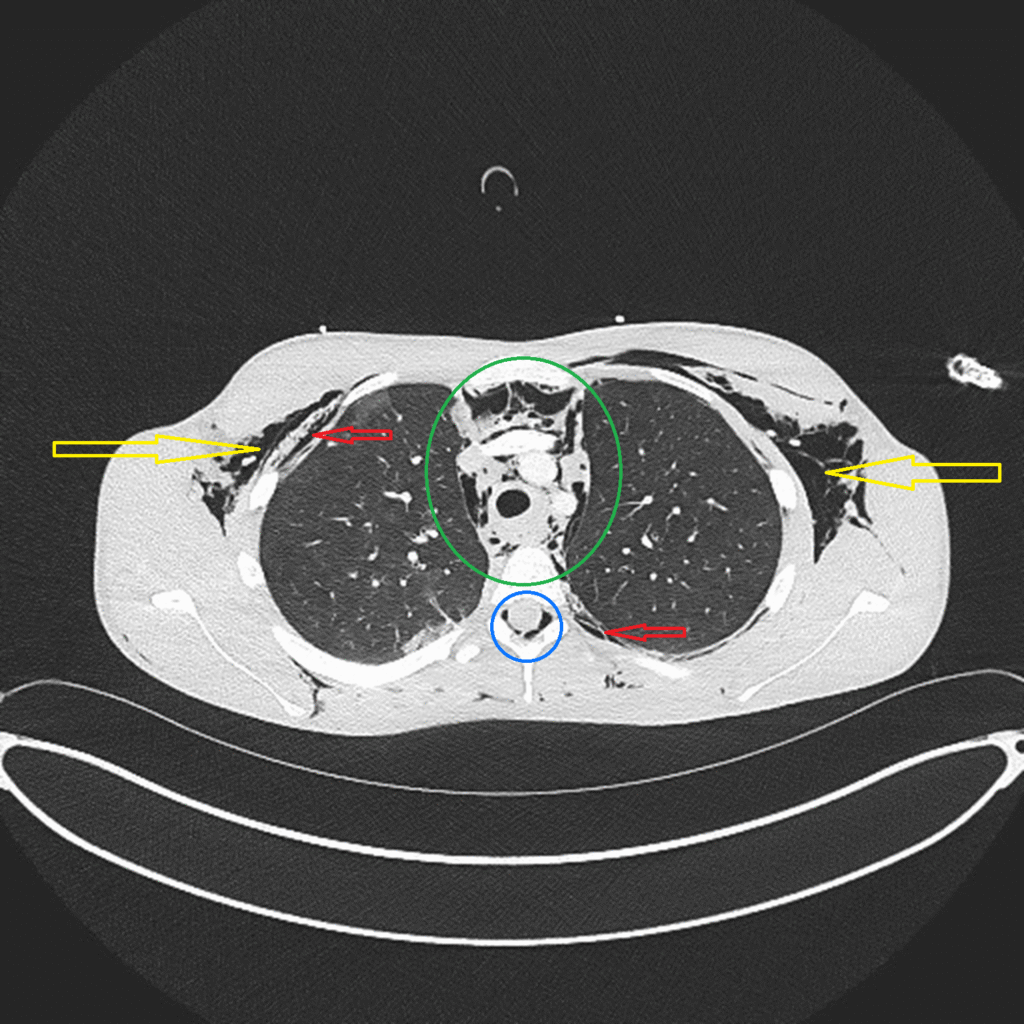

A CT scan allowed medics to diagnose ‘air leak syndrome’, in which pockets of gas or air had collected in parts of the body including the spinal canal, between the lungs, and under the skin.

Air leak syndrome is, as yet, not formally recognised as one of the conditions which constitutes e-cigarette or vaping associated lung injury (EVALI), but doctors believe the young person’s use of cannabis and vapes is a likely cause* of internal damage to their food and/or wind pipe, and in turn this led to pockets of air collecting outside of their lungs.